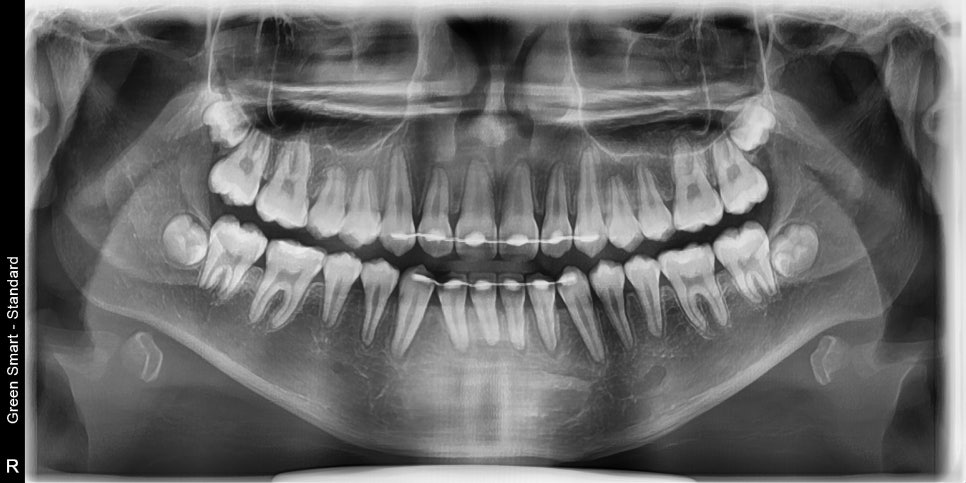

2023.4.18.에 처음 내원해서 23년6월초부터 치료를 시작한 아이입니다.

치료의 마무리는 2024.11.11.에 마무리 했습니다.

약 1년 5개월정도 진행했습니다.

교정 치료 중에 화살표 최후방 치아가 맹출하여,

이 치아를 배열하는 과정에서 치료가 조금 더 길어지긴 했습니다

최후방 치아가 나올때 약간 삐뚤게 나옴으로 인해 1회 재제작을 했습니다.